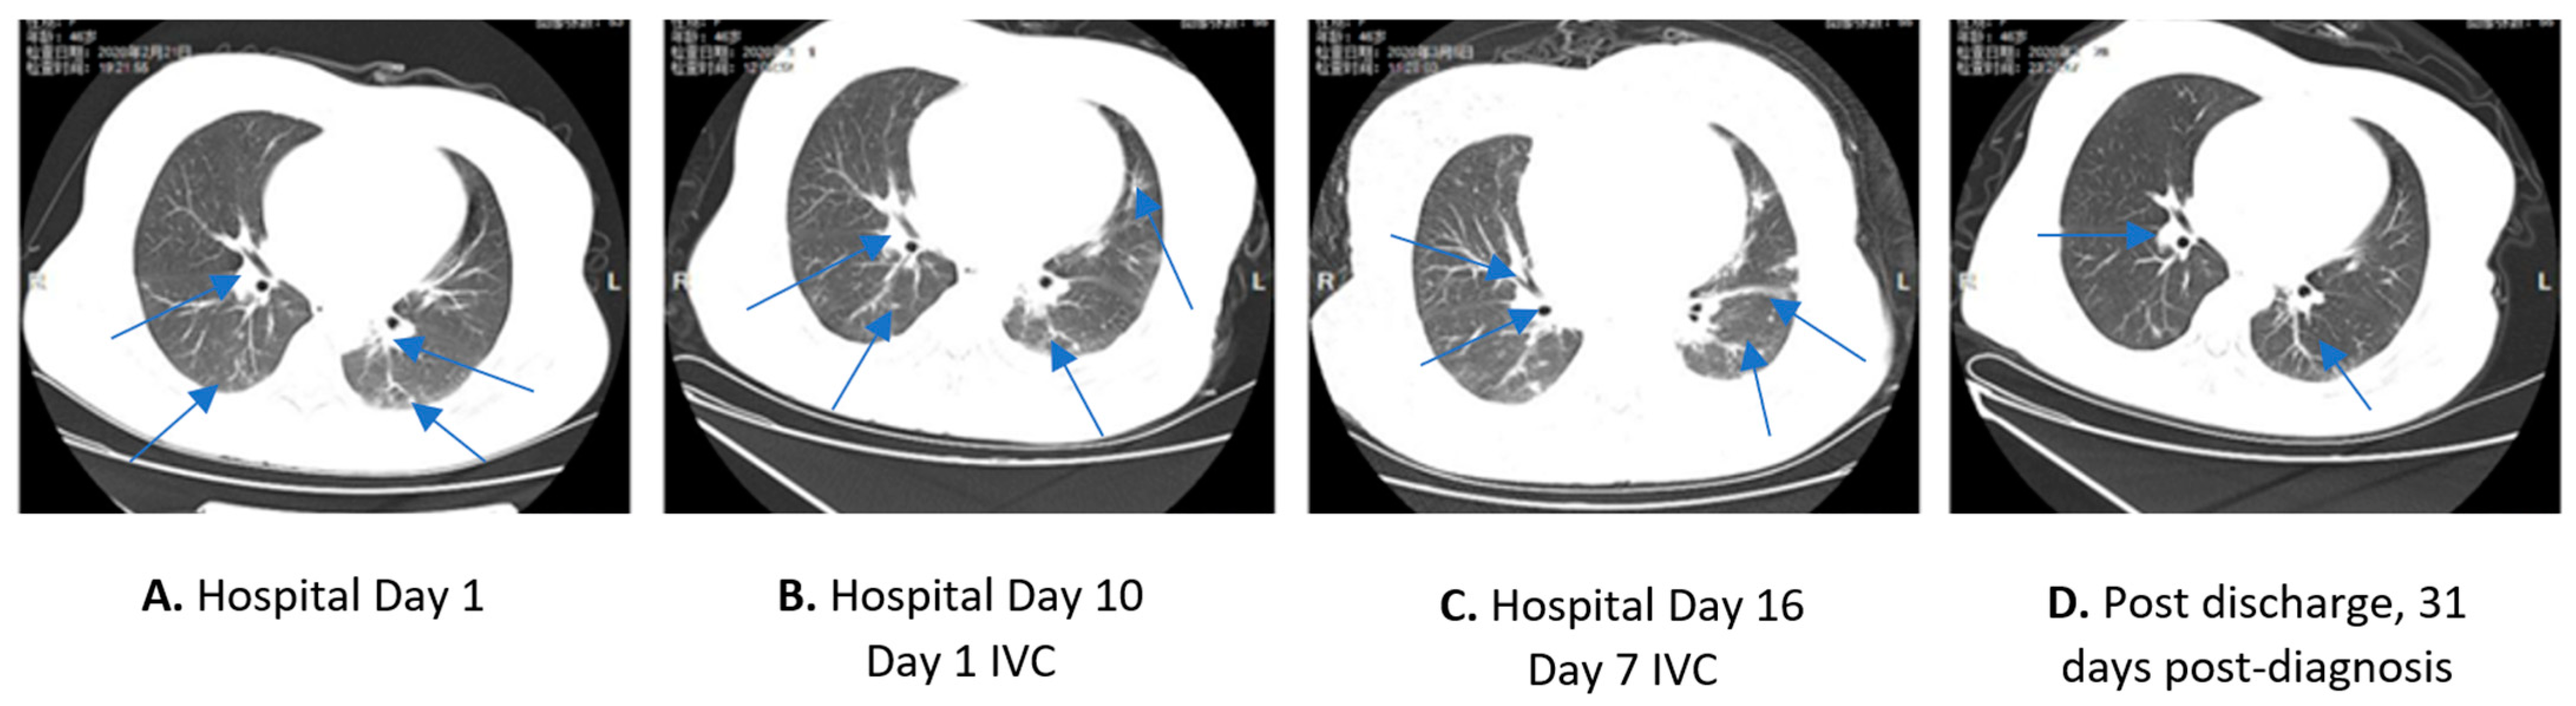

2.1. Case 1